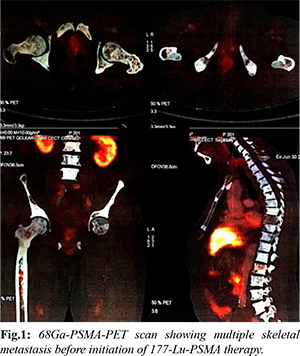

A 66-year-old male with diabetes mellitus and hypertension was diagnosed with metastatic carcinoma prostate in July 2017. His Gleason’s score was 7, with a base line sPSA of 490 ng/mL, and bone scan suggestive of multiple skeletal metastasis in humerus, scapula, sternum, multiple cervical, dorsal and lumber vertebrae. He underwent bilateral orchidectomy in August 2017 and was started on monthly zoledronic acid. In the initial 1st year, he had good clinical and biochemical response on serial sPSA, done every 3 months with a nadir PSA of 1.37 ng/mL in April 2018. He had PSA progression (sPSA: 6.73 ng/mL) in October 2018 and was started on abiraterone 1000 mg once daily and prednisolone 5 mg twice daily in December 2018. But in April 2019, due to further rise in sPSA (12.82 ng/dL), abiraterone was stopped, and enzalutamide was started. After 4 months of enzalutamide therapy, the patient was found unresponsive with continuous rise in sPSA (218 ng/mL) and hence in July 2019 enzalutamide was stopped. He was then started on chemotherapy with injection docetaxel at a dose of 75 mg/m2, 3 weekly for 6 cycles from July 2019 to November 2019. He showed further biochemical, clinical and radiological progression just after one month of completion of chemotherapy (sPSA: 458 ng/mL in Dec 2019). 68Ga PSMA PET CT scan was done in December 2019 which showed diffuse PSMA expression in prostate gland, bilateral humerus, lumber vertebra and sacrum and bilateral femur; while non PSMA avid lesion were found in bilateral humerus, scapula, clavicle, sternum, all ribs and multiple vertebrae and PSMA avid multiple foci in marrow of bilateral femur [Fig.1]. His genomic analysis revealed low tumor mutation burden score with stable MSI and no mutation in germline or somatic DNA repair pathway.